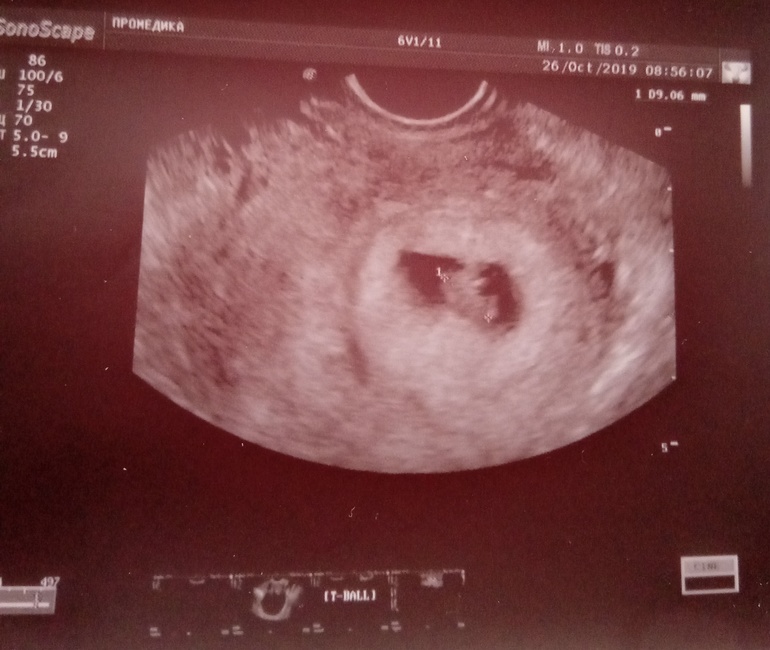

Подруга попросила узнать, поскольку тут знающие люди есть: узи на 5+6

Посмотрите, пожалуйста))

Контуров хориона. Он ведь на узи виден как более светлая область вокруг плодного яйца, верно?

Ого, не думала, что хорион такой большой. А это нормально, что контуров не видно?